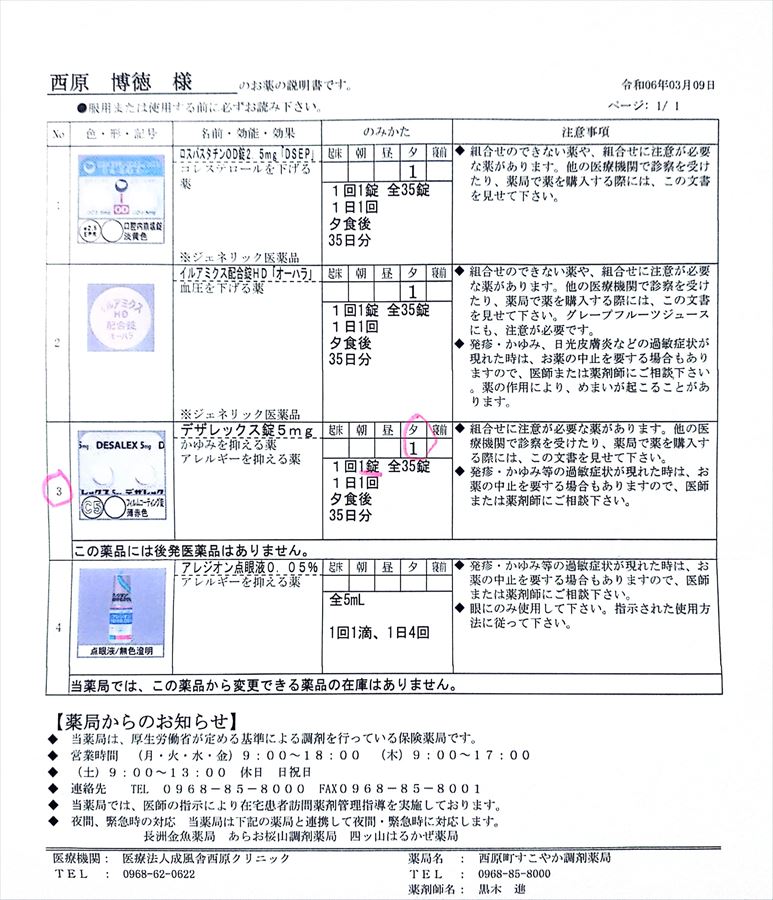

2024.3.9 鼻炎と目のかゆみがひどく、オロパタジン⇒デザレックス&点眼薬 アレジオン に変更 2.10 血液検査結果